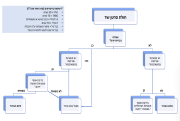

| 19:51, 18 בפברואר 2024 | חולה סרטן ערמונית-לבלב.png (קובץ) |  |

110 קילו־בייטים | Roeitul | 1 | |

| 19:51, 18 בפברואר 2024 | חולה סרטן ערמונית.png (קובץ) |  |

183 קילו־בייטים | Roeitul | 1 | |